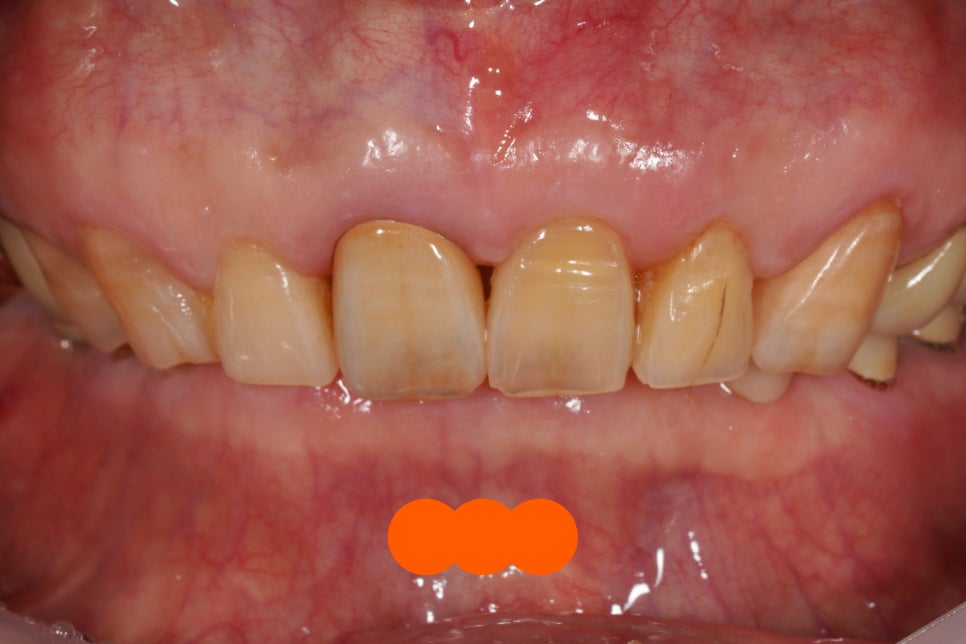

처음 오셨을 때 사진

스토리가 있는 치아를 만나니

제대로 잘 치료해드리고 싶다는 욕심이 듭니다.